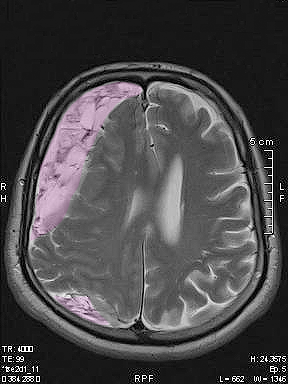

Τα χρόνια υποσκληρίδια αιματώματα είναι αιματώματα τα οποία αναπτύσσονται στην επιφάνεια του εγκεφάλου καθυστερημένα (εβδομάδες έως και μήνες) μετά από μια, συνήθως ήπια, κάκωση της κεφαλής, κυρίως σε ασθενείς ηλικιωμένους, με διαταραχές της πήξεως του αίματος ή λαμβάνοντες αντιπηκτική ή αντιαιμοπεταλιακή φαρμακευτική αγωγή όπως η ασπιρίνη. Η ανάπτυξή τους είναι αργή και το ίδιο ισχύει για τα ποικίλα συμπτώματά τους. Η θεραπεία στα μεγάλα ή προκαλούντα συμπτώματα χρόνια υποσκληρίδια αιματώματα είναι κατά κανόνα χειρουργική με κρανιοανάτρηση ή μικρή κρανιοτομία και παροχέτευση του αιματώματος. |

Αξονική ή μαγνητική τομογραφία εγκεφάλου. Σε ορισμένες περιπτώσεις τα χρόνια υποσκληρίδια αιματώματα μπορεί έχουν την ίδια πυκνότητα στην απεικόνιση με το εγκεφαλικό παρέγχυμα ή να βρίσκονται ακόμη σε πρώϊμο στάδιο ανάπτυξης όσον αφορά στο μέγεθος και τη σύσταση, και αυτό μπορεί να καταστήσει την διάγνωση πιο δύσκολη.